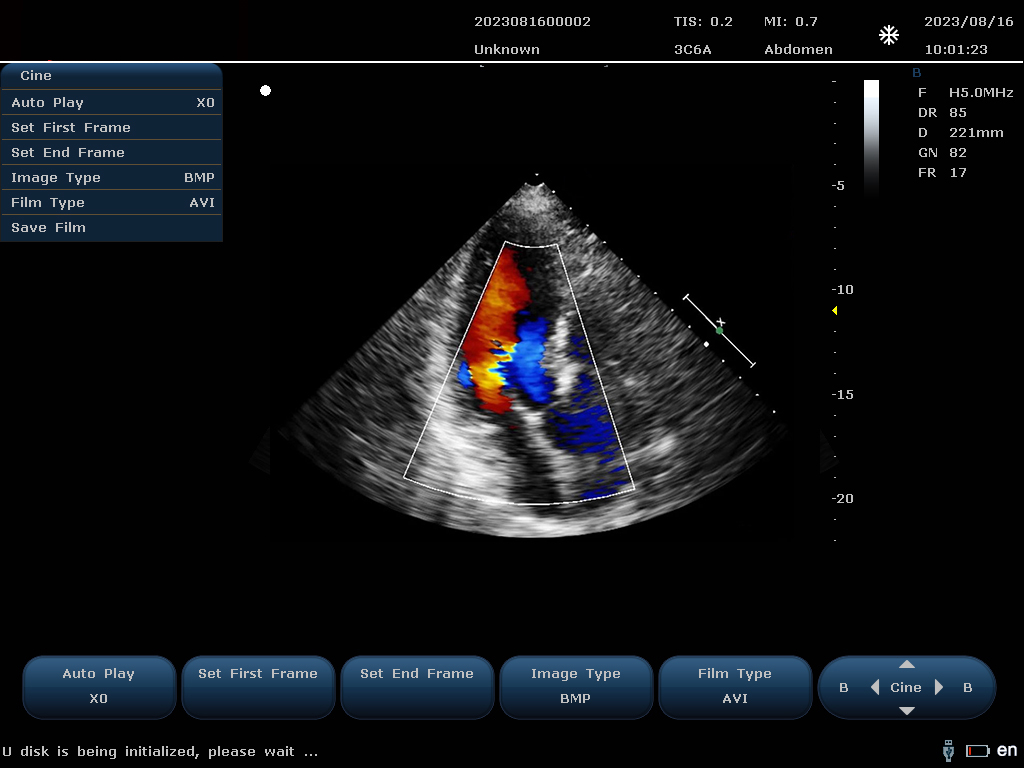

設備通過檢測這些頻移信號,并利用復雜的信號處理技術,包括傅立葉變換等,分析血流的方向、速度和分布。彩色編碼后,血流信息被疊加在傳統(tǒng)的黑白超聲二維圖像上,形成彩色多普勒圖像,直觀顯示血流動態(tài)。

最終,這些信息轉化為圖像顯示在屏幕上,醫(yī)生可以根據(jù)圖像中血流的顏色(通常紅色代表血流朝向探頭,藍色代表遠離探頭)和亮度來判斷血流的性質和異常情況,如血流速度增快可能指示狹窄,無血流區(qū)域可能意味著阻塞等。